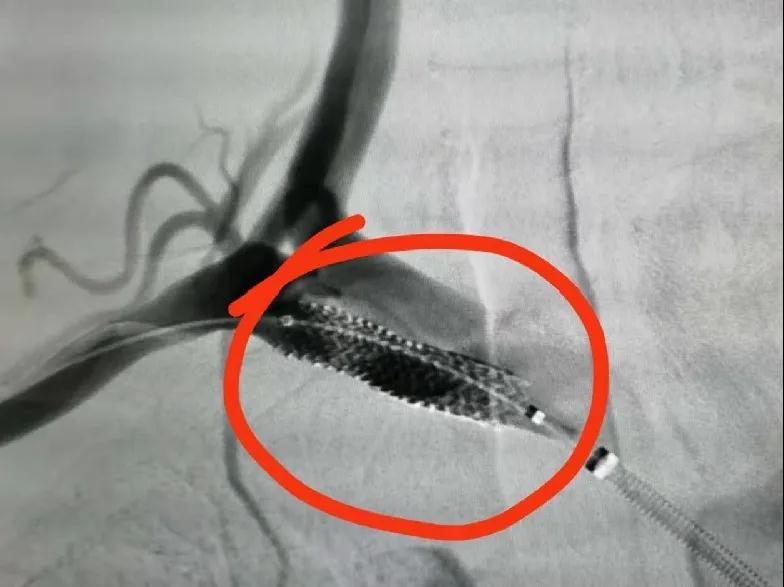

濱海康達醫院 | DSA微創介入治療技術再添新病種

近日,濱海康達醫院成功為一位鎖骨下盜血綜合癥伴右鎖骨下動...